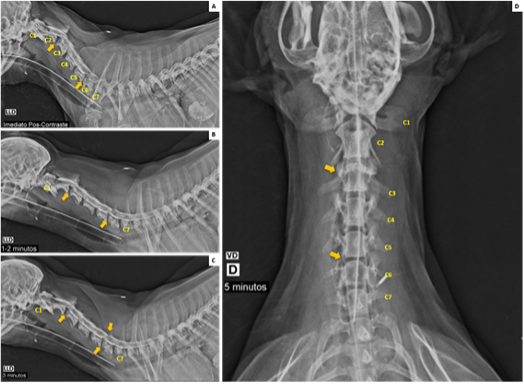

Primary T-Cell Lymphoma of the Prostate in a Dog – Case Report

Marina Laudares Costa, Carlos Eduardo Fonseca-Alves, Gustavo Garkalns de Souza Oliveira, Ana Paula Massae Nakage-Canesin, Paula Christine Bonadio Rezende, Thiago Demarchi Munhoz